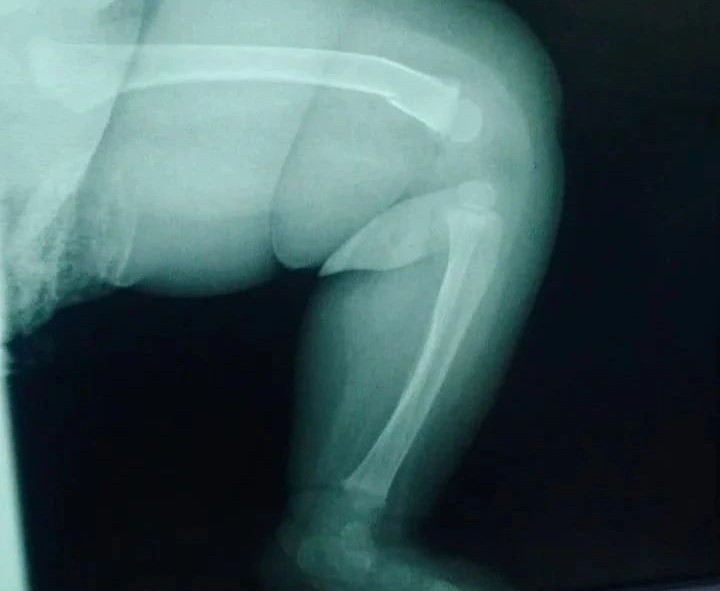

На запрос редакции Liter.kz в больнице Щучинска подтвердили, что ребенка с закрытым переломом левого бедра со смещением направили в больницу Кокшетау.

22 декабря в 19:29 родители ребенка обратились в приемный покой ТОО “Авиценна-Бурабай” после полученных травм в результате падения родителя с ребенком в канализационный люк. Родителям предложено проведение репозиции под наркозом. От предложенной помощи родители отказались. Ребенку была проведена гипсовая иммобилизация и направлен в травматологическое отделение МОДБ город Кокшетау, – сказано в сообщении.